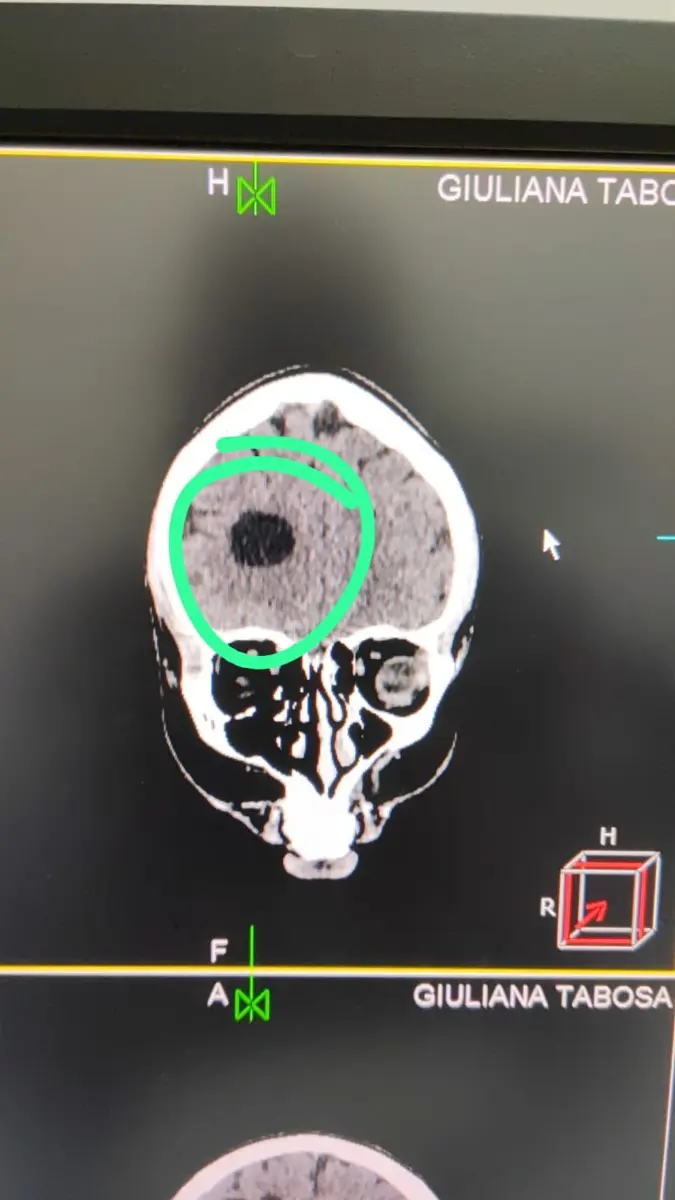

A jovem no dia 23 de agosto, apresentou mal-estar durante uma sessão de exercícios em uma academia. Alertada por uma amiga estudante de medicina, ela se submeteu a uma tomografia de urgência que revelou uma mancha preocupante em seu cérebro. O médico responsável pela avaliação explicou que ela tem um cisto no lado direito próximo ao ventrículo, além de uma veia anormal do lado esquerdo do cérebro.

“Estou com um cisto no lado direito próximo ao ventrículo e uma veia anormal do lado esquerdo do cérebro. Vamos tentar um tratamento nos próximos 3 meses. Se o cisto não diminuir de tamanho ou a dor não passar, serei submetida a uma cirurgia. Enquanto isso, fui instruída a ter repouso absoluto e evitar qualquer tipo de emoção intensa. No entanto, a opção mais viável pode ser a cirurgia, devido à proximidade do cisto com os ventrículos”, compartilhou Giuliana ao ContilNet.